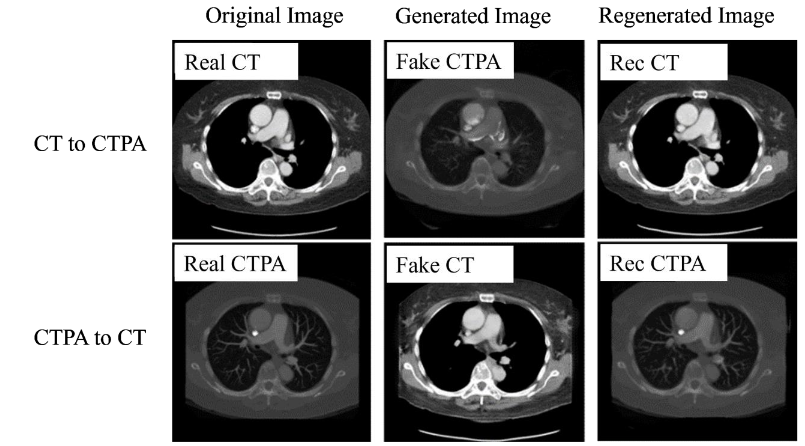

In the generation results of CTPA_CycleGAN model (ResNet), as shown in

, we can find that the simulated CTPA image Fake_B generated by generator A has a high degree of similarity to the real CTPA image Real_B, and the vascular imaging is also the best among all models. A point that is worth discussing is the Rec_B image, which is a simulated CTPA image generated by the CTPA image through generator network B and then generated by generator network A. Its similarity to Real_B is even higher than that of Fake_B, and there is almost no difference with the original image.